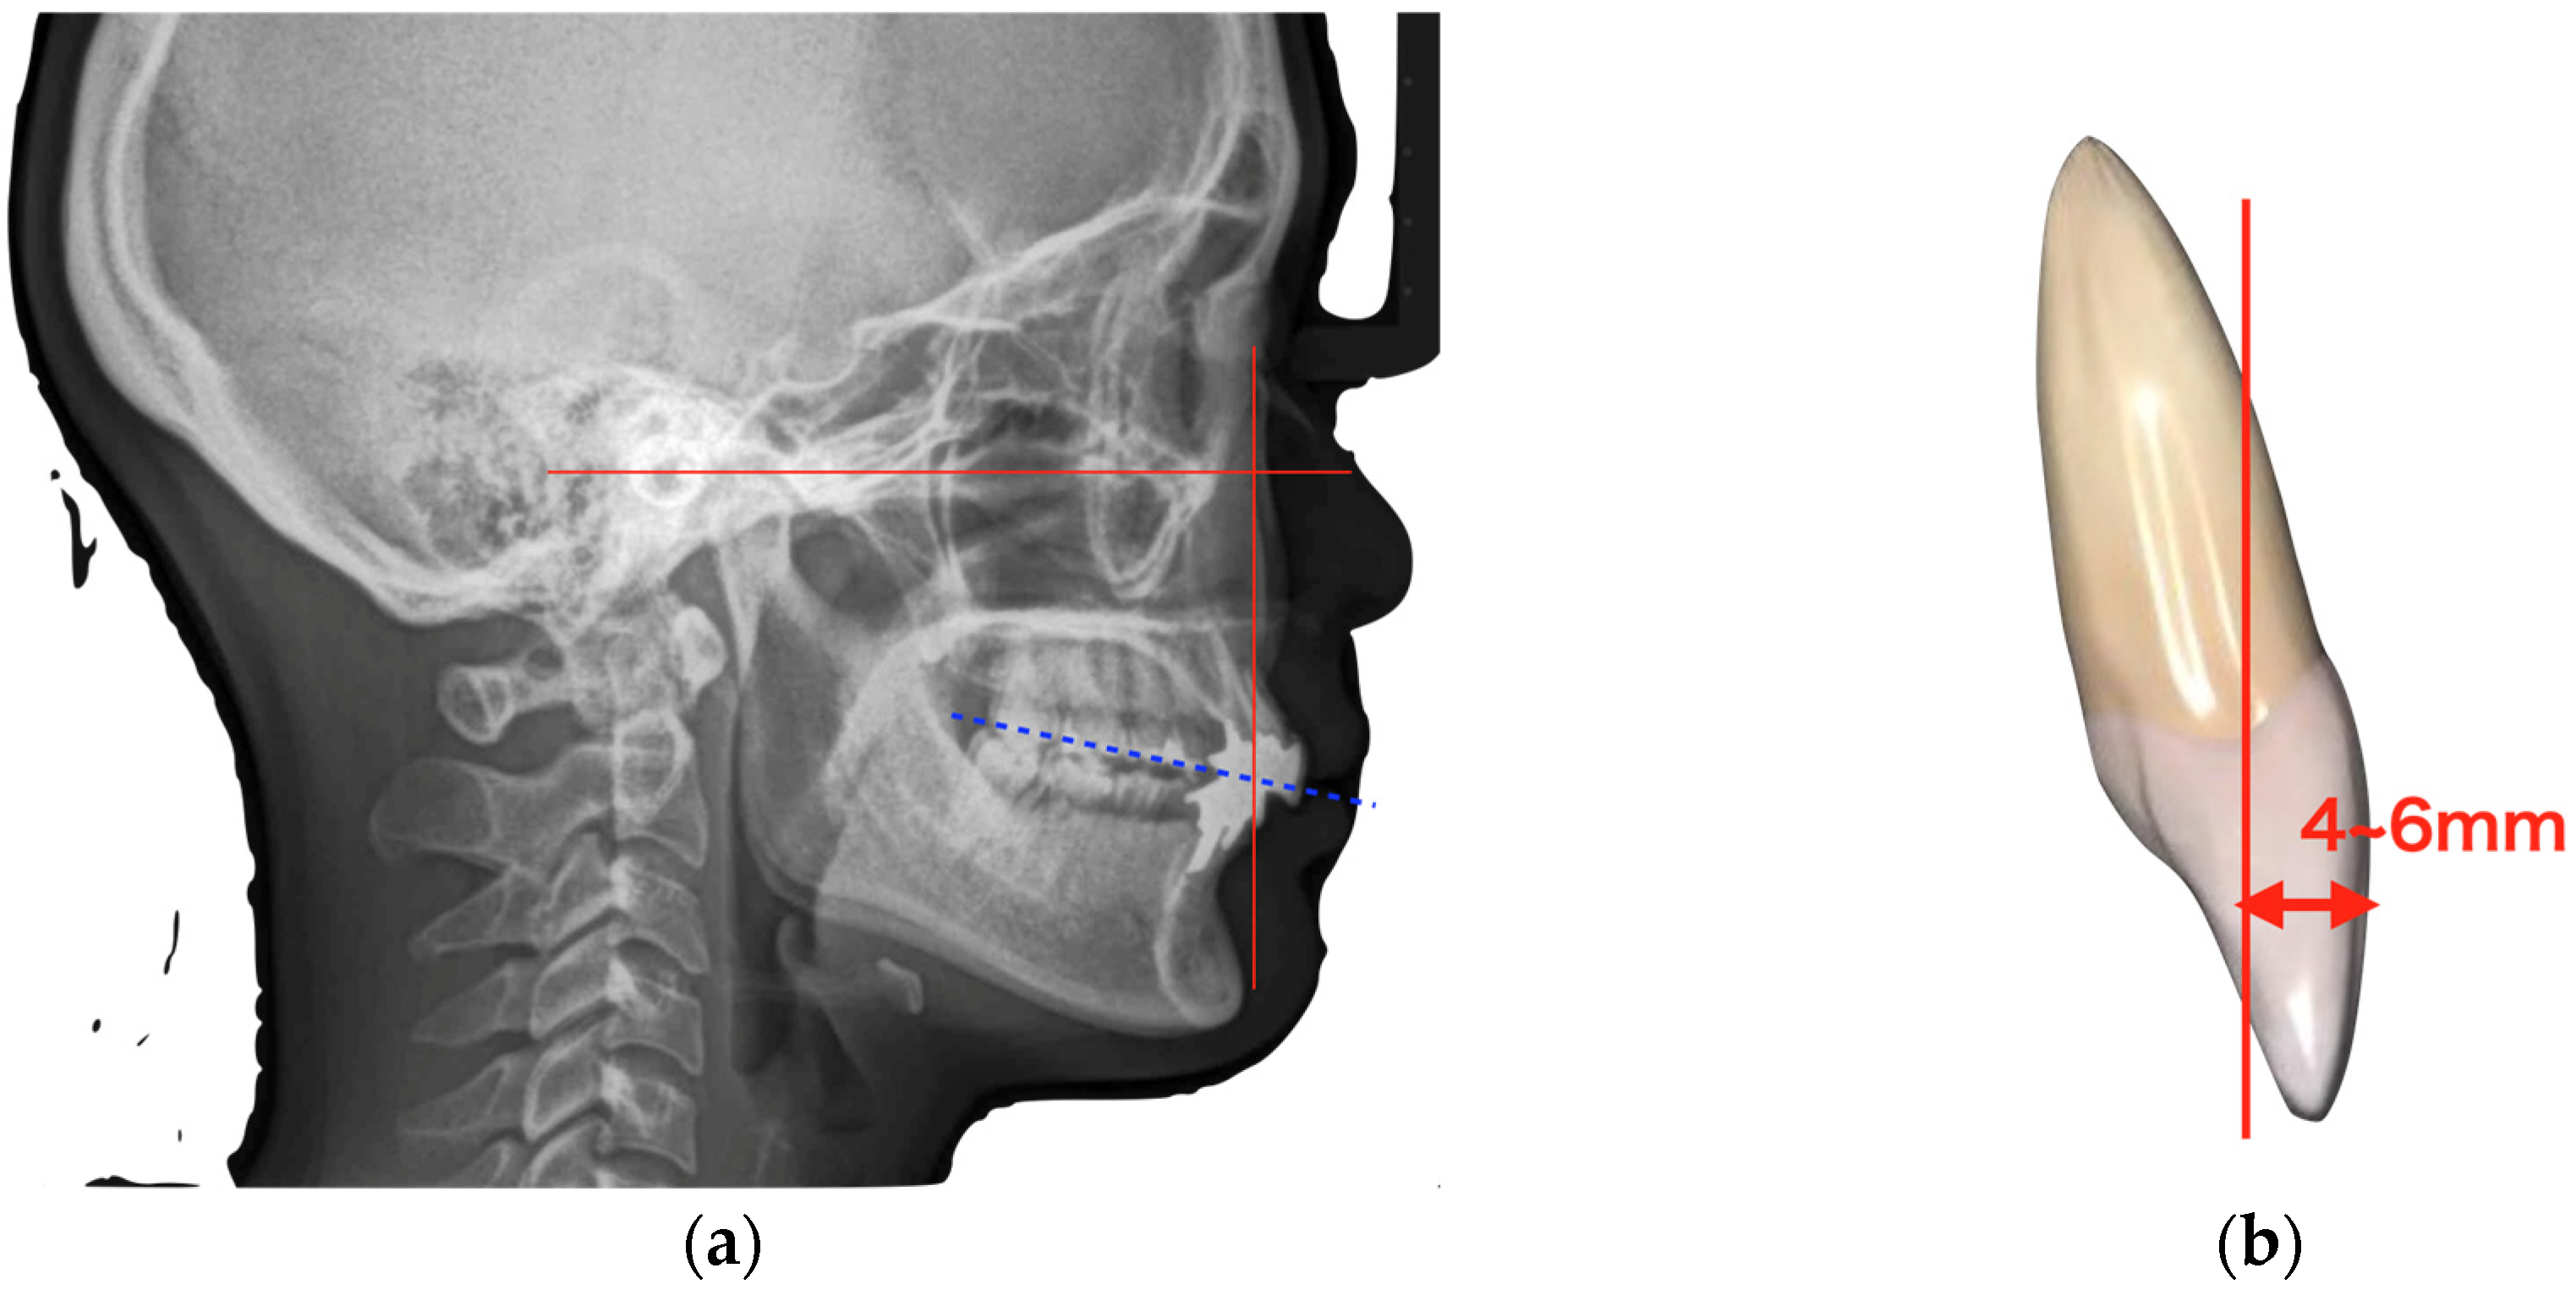

At the time of the initial examination, the porcelain-fused-to-metal restorations of the maxillary bilateral central and maxillary left lateral incisors were detached, and the maxillary left lateral incisor was affected by caries (Figure 1). A sinus tract was found on the buccal side of the maxillary right central incisor. Crowding was also observed in her dentition. The maxillary bilateral second molars had been extracted, and the maxillary right first molar and mandibular bilateral first molars were under treatment, resulting in a significant decrease in occlusal support in the molar regions (Figure 1 and Figure 2). Periodontal examination revealed extensive plaque accumulation throughout the dentition, with a plaque control record of 75% (Figure 3a). Periodontal pockets of 6–7 mm and suppuration were observed in the maxillary bilateral central incisors. Radiographs showed radiolucency around the roots of the maxillary bilateral central incisors and a fracture line around the center of the roots (Figure 3b). Marked alveolar bone resorption was observed around multiple teeth, including the maxillary bilateral lateral incisors. Based on the examination results, the patient was diagnosed with bilateral maxillary central incisor root fracture, malocclusion (classified as Angle class 1 with crowding), and stage 4 periodontitis (grade C).

Figure 3. Results of initial periodontal examination (a) and dental radiographs (b).